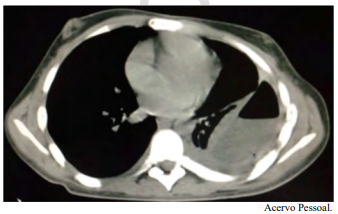

Um paciente do sexo masculino, jovem de 21 anos de idade, com diagnóstico prévio de esquizofrenia, foi internado para investigação de alteração na tomografia de tórax, conforme a imagem a seguir. A clínica apresentada era perda de peso, febre vespertina, tosse e um episódio de hemoptise. É familiar contactante de paciente com tuberculose ativa.

Com base nesse caso clínico e nos conhecimentos médicos correlatos, julgue o item a seguir.

O principal diagnóstico diferencial da condição apresentada pelo paciente é a sarcoidose.